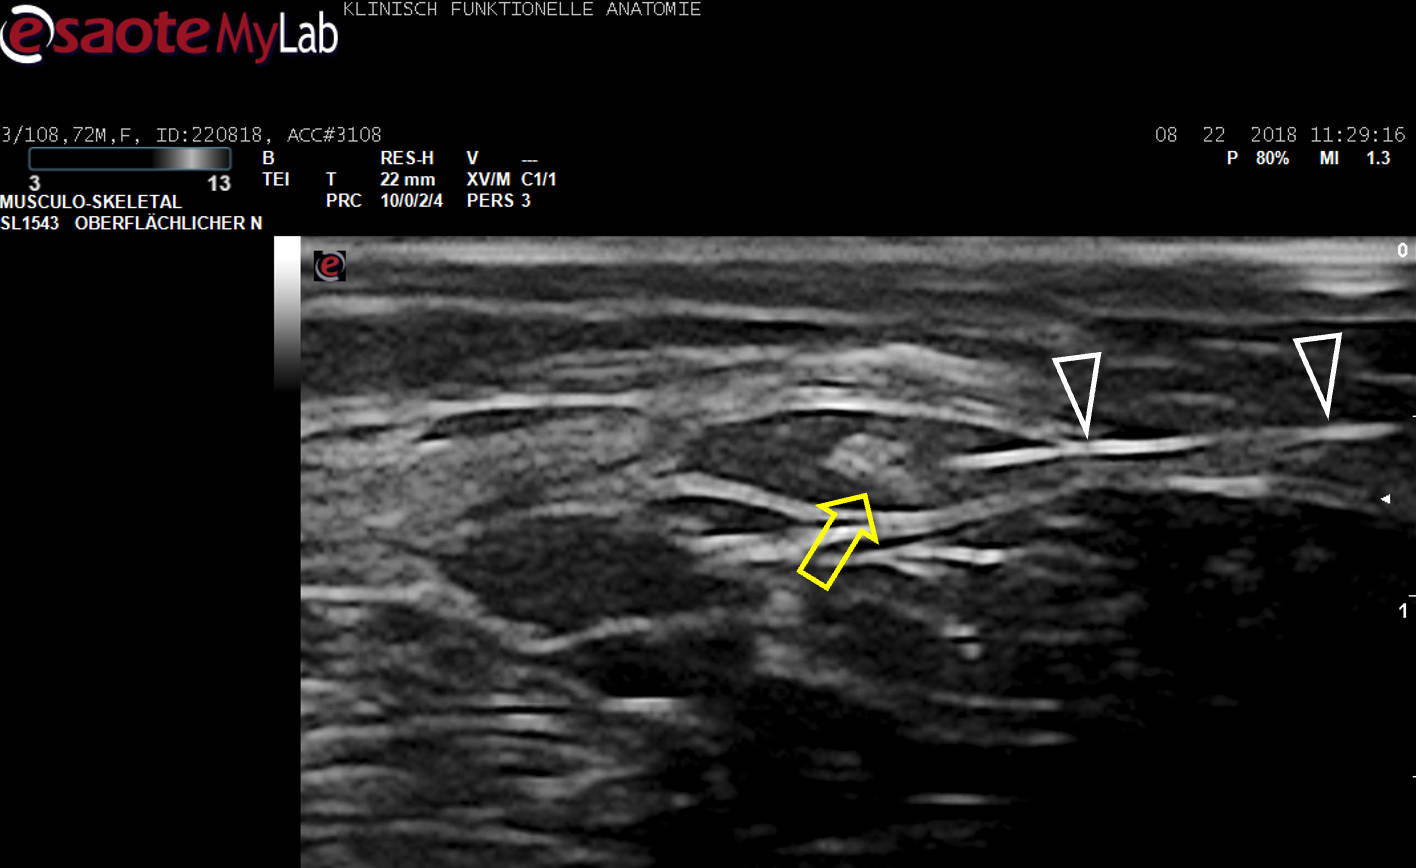

US-Darstellung und experimentelle Blockade (Pfeilköpfe: Nadel) des N. cutaneus femoris lateralis an einer Körperspenderin. Mittlerweile gängige Anwendung in der Regionalanästhesie und Schmerztherapie

Der hell erscheinende N. cutaneus femoris lateralis (Pfeil) wird am Oberschenkel in seinem „fettgefüllten Flachtunnel“ (im US dunkel!) am leichtesten aufgefunden: “POV“ (Point of Optimal Visibility) nach Prof. Moriggl.